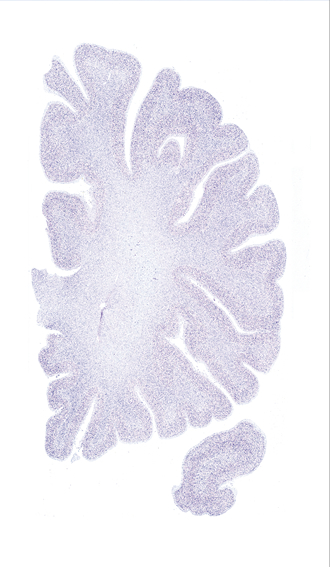

Hi-Resolution Sections · Cells (Nissl Staining) · Virtual Microscopy

Frontal sections (Nissl) from the Atlas Brain:

Slice ID:

r2-0670

Plate NR:

09-10

Position:

-21,6 mm